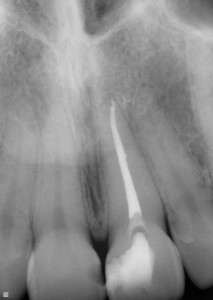

The dentist will examine the tooth and an x-ray is necessary to inspect the root for possible infection.

Root treatment done

White line indicating

root treatment